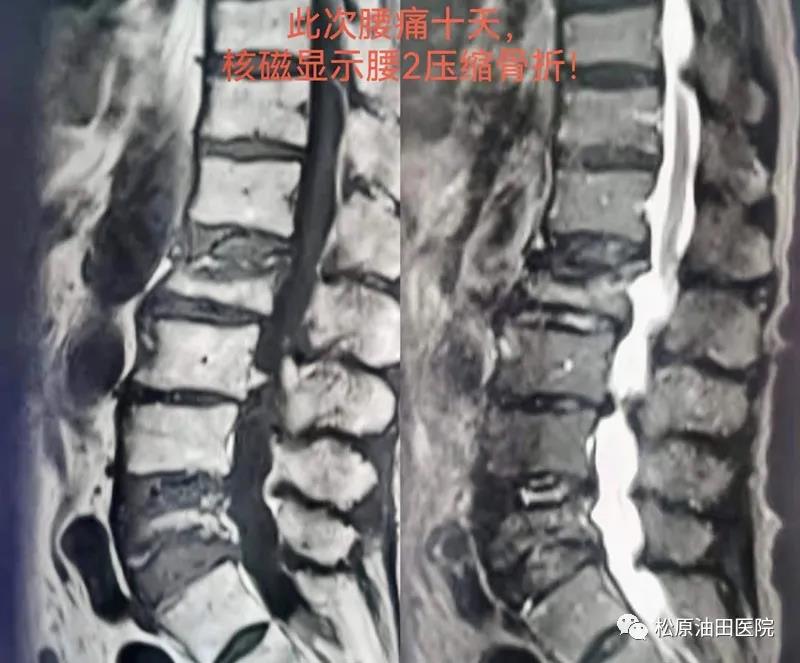

据了解,骨一科已经开展椎体成形术(PVP)十余年,一直以来,手术都是在C臂透视引导下进行的,经过多年的研究和探索,手术时间已经可以控制在半小时左右,其中穿刺手术时间约15至20分钟,等待骨水泥硬化时间约12分钟。油田医院今年引进了G臂X光机后,大大缩短了穿刺手术时间。23日手术的这位79岁女性患者,有2个月前腰5压缩骨折病史,腰椎X光片及核磁显示:腰5变扁,椎体内有异常信号。患者新发腰痛,考虑其他椎体骨折可能,复查腰椎核磁,结果显示腰2椎体压缩骨折,经全科讨论后,明确临床诊断为腰2椎体压缩性骨折和重度骨质疏松症,治疗首选椎体成形术,于是这位患者成为骨一科第一例G臂引导下PVP手术病人。